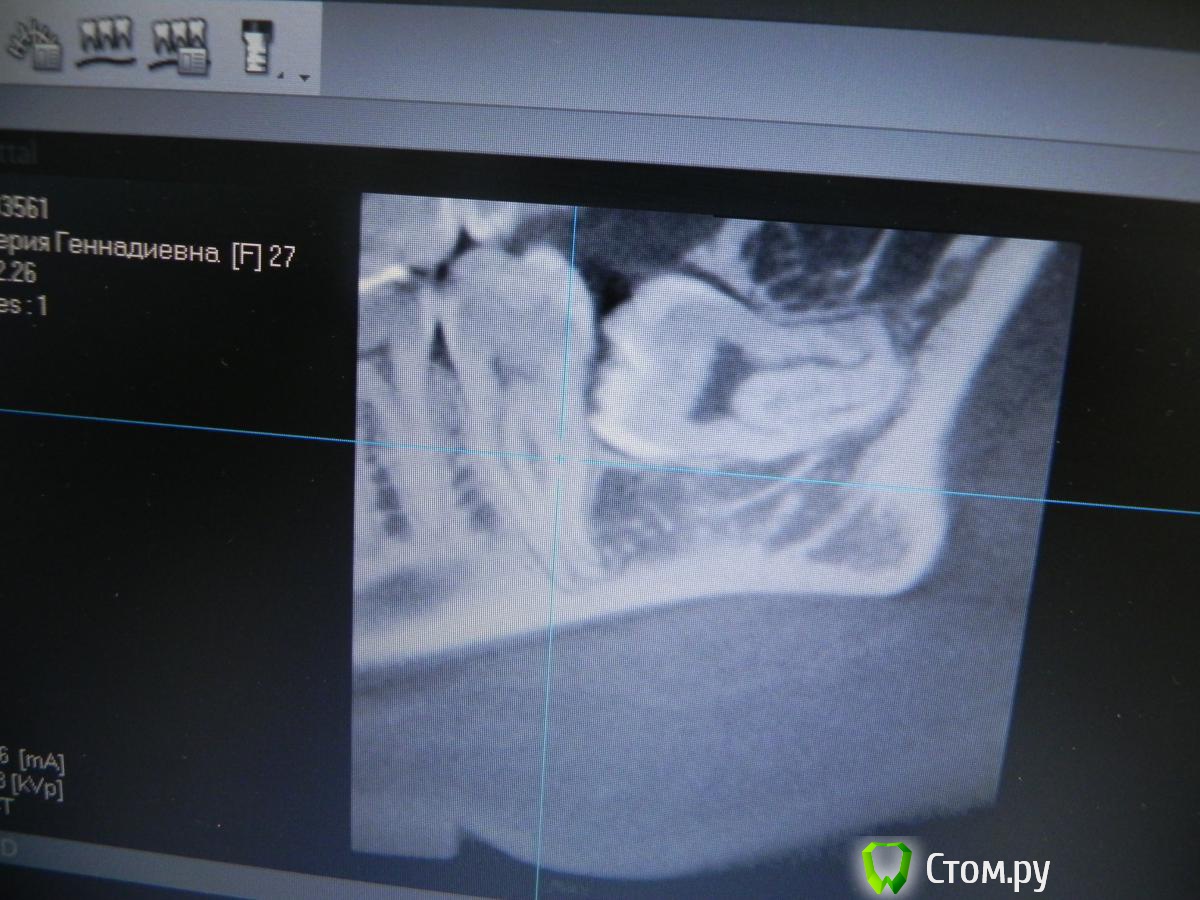

red_butler Опубликовано 24 мая, 2014 Поделиться Опубликовано 24 мая, 2014 Началось сегодня утроhttp://s019.radikal.ru/i608/1405/89/12be27e14435.jpghttp://i016.radikal.ru/1405/c4/88dd538cb75b.jpg 11 Ссылка на комментарий

Kostoprav Опубликовано 10 июня, 2014 Поделиться Опубликовано 10 июня, 2014 вот такой клад откопал недавно) 2 Ссылка на комментарий